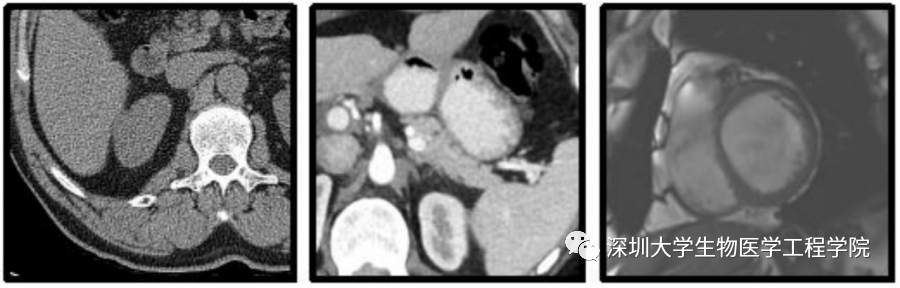

这批验证码全名为“MedCAPTCHA医学图像验证码”,由腾讯安全平台部和深圳大学生物医学工程学院合作研发,验证中所用到的图片,全部来自于临床上真实的脱敏医学图像,通过验证码的形式开放给广大网民自愿体验及参与标注。

基于这一想法,腾讯安全平台部防水墙团队与深圳大学医学工程学院高毅教授团队合作研发并灰度上线了“MedCAPTCHA医学图像验证码”公益实践项目,供广大网民自愿体验。研发人员把深圳大学提供的未经标注的海量脱敏医学图像,以图片验证码的形式上线防水墙官网。

在这个自愿体验的安全验证环节中,用户只需要参照给出的图片示例“照猫画虎”,移动鼠标在图片上进行简单勾画,就能完成在线验证,并成功提供了一次医学图像标注答案。